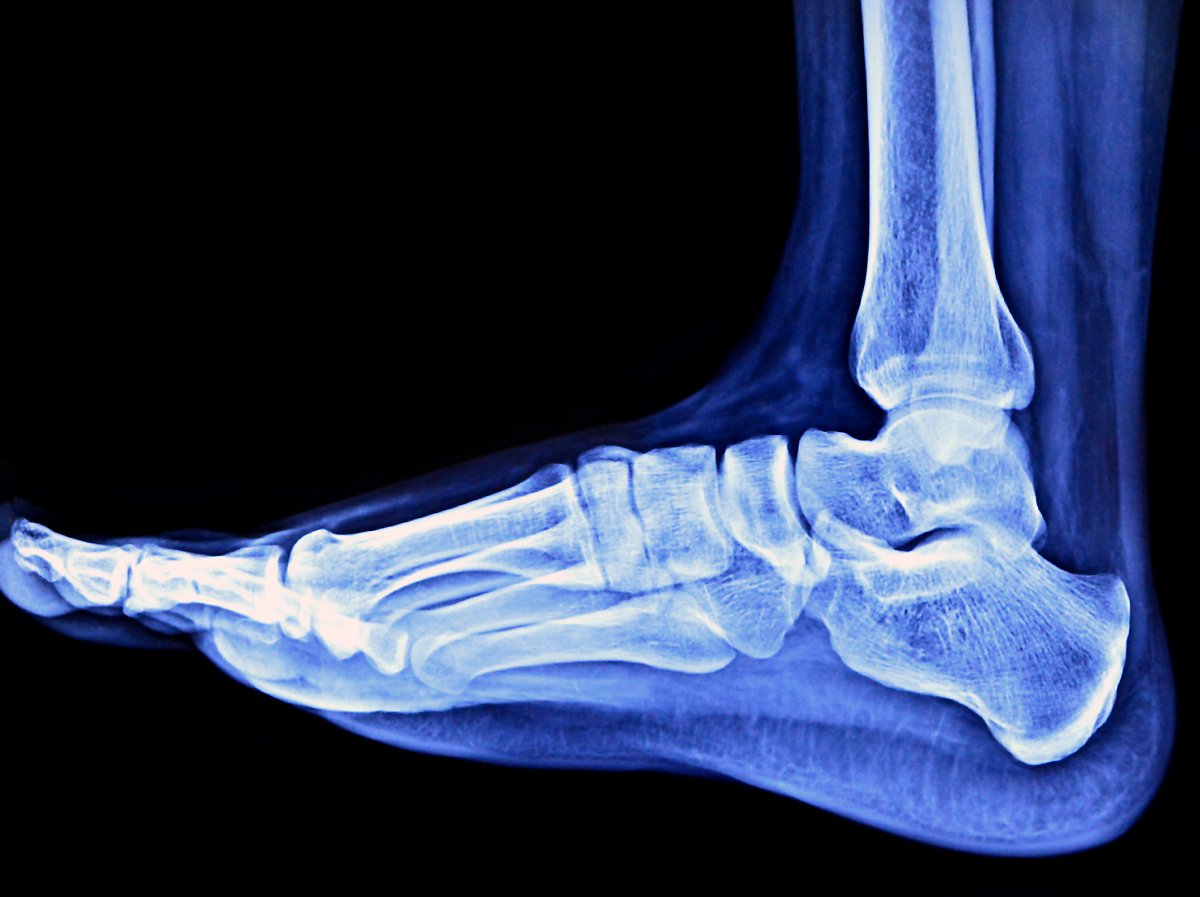

발목 염좌의 진단

골절 여부는 신체 검진과 단순 방사선 촬영(x-ray)을 통해 판단합니다. 만성 불안정성이 의심되면 발목에 스트레스를 가한 뒤. 단순 방사선 촬영으로 인대 손상을 유추할 수 있습니다. 간혹 동반된 기타 연조직 손상 정도와 인대의 파열 정도를 정확하게 파악하고자 MRI 등의 검사를 진행하기도 합니다.